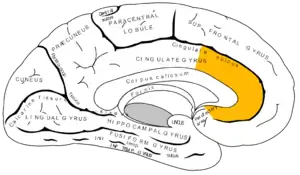

![]() Medial surface of left cerebral hemisphere, with anterior cingulate highlighted | |

In the human brain, the anterior cingulate cortex (ACC) is the frontal part of the cingulate cortex that resembles a "collar" surrounding the frontal part of the corpus callosum. It consists of Brodmann areas 24, 32, and 33.